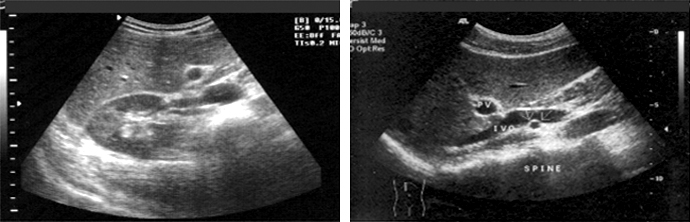

갑상선 세침 흡인 검사

갑산선 세침 흡인 검사는 초음파 진단 시 결절이 있는 경우 암 여부를 진단하기 위한 검사입니다.

주사기로 결절 부위의 조직을 얻는 검사로 매우 가는 주사바늘을 이용하여 통증이나 부작용이 없고 간단하고 안전한 장점이 있습니다.